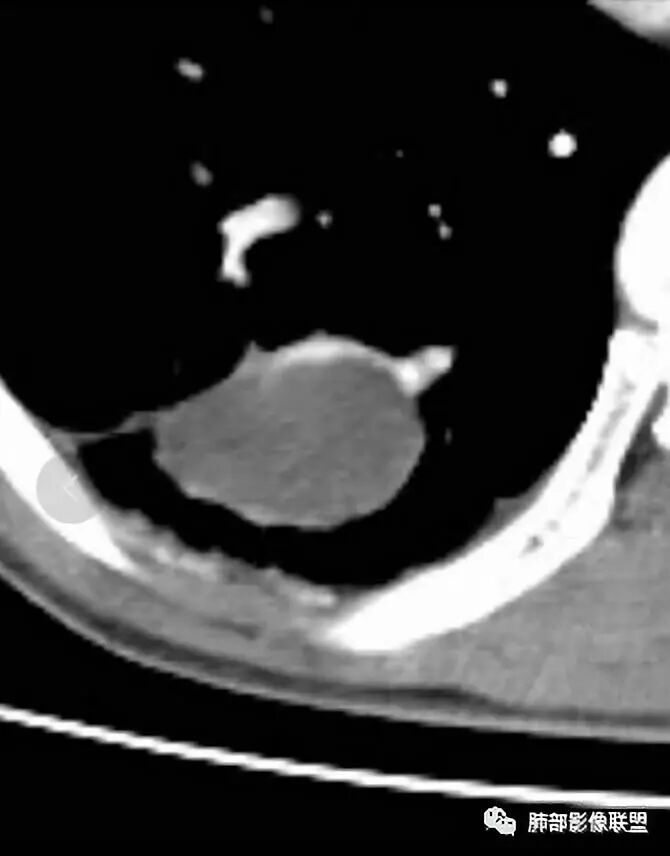

右肺下叶囊性病变,边缘光滑,薄环状强化,内壁较光滑

南边:周围病灶提示应该是慢性,因为有肺气肿,病灶密度偏高:问题是囊性病变该考虑啥?

第四,病变为薄壁环状强化,就两种可能,

1 是病变内为囊性成分,即囊肿,周围病变考虑合并感染;      2 是病变内是干酪坏死,周围是薄壁强化,然后是一点纤维组织,再周围是一些结核的病灶;

但是有些疑惑:

首先周围病变肯定是感染性病变;索条状的,但是囊肿伴这样感染,真的很少见;

其次病变周围有索条、肺气肿,这些慢性病的改变;还有就是形态,似乎是稍长点的形态;这几点就更符合结核的表现,但是周围病灶没有树芽征,都是索条;结核这样子的干酪样坏死,也少见,壁薄呈这样,就一层纤维;附近的血管又这么粗;

但是我们先把方向锁定在炎性病变;囊肿伴感染还是结核,这两个在图片上各自特点都有,从目前条件无法完全典型的分辨出来;但是还是倾向于囊肿合并感染。